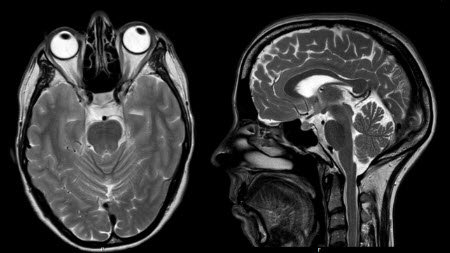

Voorbeeld van plakjes door het hoofd, van boven en opzij

Het MRI-apparaat is eigenlijk een hele sterke magneet. Het apparaat is gemaakt in de vorm van een tunnel. In deze tunnel heeft het magnetisch veld een sterkte van 1,5 of 3 Tesla. Het menselijk lichaam bestaat voor het grootste deel uit water(protonen). Wanneer u in het apparaat ligt, richten de waterstofprotonen in het lichaam zich in de richting van het sterk magnetische veld. Dit noemen we de 'rusttoestand'. Door een radiopuls de MRI in te sturen, kunnen de waterstofprotonen heel even uit hun rusttoestand worden gebracht (resonantie). Deze radiopulsen zijn te vergelijken met het signaal dat een zender naar uw radio stuurt. De radiopuls draagt een klein beetje energie over aan de protonen.

Na de korte verstoring vallen de waterstofprotonen weer langzaam terug naar de rusttoestand (in de richting van het magnetisch veld). De opgenomen energie wordt vervolgens weer als signaal uitgezonden door de waterstofprotonen, wanneer deze terugvallen naar de rusttoestand. Dit signaal wordt gemeten door antennes en door een computer omgezet in beelden. Het ene weefsel bevat veel waterstofprotonen, het andere minder. De tijd die de waterstofprotonen nodig hebben om na de radiopuls terug te vallen naar de rusttoestand, verschilt per soort weefsel. Hierdoor kan men op de beelden de verschillende weefsels van elkaar onderscheiden. Door het maken van verschillende series met beelden (dunne ‘plakjes’ van het lichaamsdeel in diverse richtingen) kan de radioloog de diagnose stellen.

Door het gebruik van verschillende technieken kunnen de weefsels beter of juist minder goed zichtbaar worden. De foto’s (plakjes) kunnen in iedere willekeurige richting worden gemaakt. Tijdens een MRI-onderzoek worden daarom diverse soorten fotoseries (scans) gemaakt.